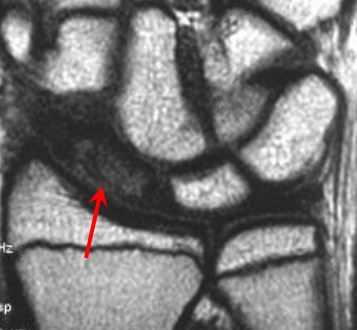

(Слева) MPT, GRE, коронарный срез: определяется травматический периферический частичный разрыв ТФХ. Этому явлению сопутствует косой перелом основания шиловидного отростка локтевой кости. Такой перелом является подострым с отсутствием смещения и относится к 1В классу с разрывом локтевой части по классификации Палмера.

(Справа) MPT, GRE, коронарный срез: определяется экскориация и уменьшение толщины № треугольного фиброзного хряща вдоль его проксимальной поверхности, с отсутствием отдельной перфорации. Этот признак соответствует дегенеративному образованию 2А класса по классификации Палмера. Обратите внимание на положительное отклонение локтевой кости. (Слева) MPT, GRE, коронарный срез: определяются уменьшение толщины и неровность проксимальной части ТФХ с хондромаляцией вдоль медиального края полулунной кости и сопутствующей субхондральной кистой. Такие признаки соответствуют образованию 2 В класса по классификации Палмера.

(Справа) МР-артрография, Т1ВИ, режим подавления сигнала от жира, коронарный срез: определяется разрыв центральной части ТФХ на полную толщину. Отмечается очаговое уменьшение толщины хряща вдоль головки локтевой и соседней полулунной костей. Также определяется разрыв полулунно-трехгранной связки. Эти признаки соответствуют травме 2D класса по классификации Палмера. (Слева) Ультрасонография в продольной плоскости: определяется разорванный треугольный фиброзный хрящ. (U = локтевая кость, R = лучевая кость) УЗИ в реальном времени может быть, в частности, информативно при отведении кисти в лучевом направлении.